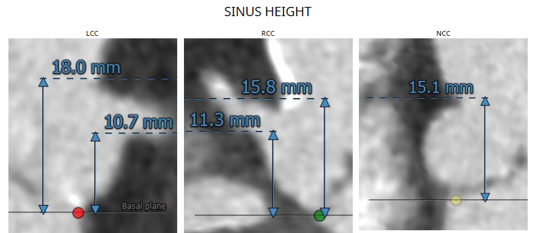

患者资料:84岁女性,既往有高血压、糖尿病、冠心病病史,5年前曾行PCI手术,此次入院诊断为主动脉瓣重度狭窄伴关闭不全,瓣环内径18.5mm,AV Vmax 3.79m/s,LVOT 23.7mm,有效瓣口面积0.6m²。

考虑到患者高龄,合并多种病症,且为PCI后再行TAVR,手术存在较高的血管并发症风险,对TAVR瓣膜器械的选择提出了较高要求。经多专家、多学科讨论,罗建方、谭冠昶教授最终选择使用Evolut PRO+开展此台TAVR手术,以为患者提供最佳的手术体验和更好的手术保障。